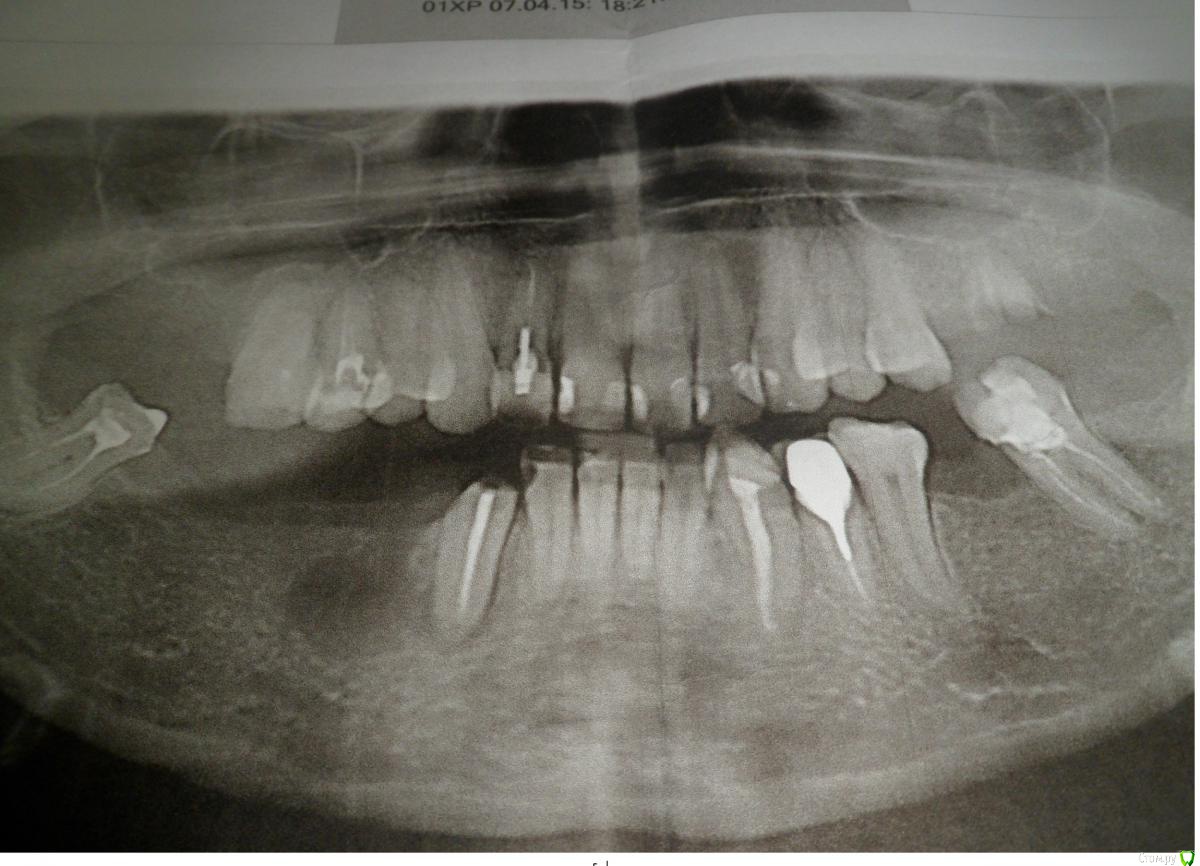

Рая Опубликовано 6 декабря, 2015 Поделиться Опубликовано 6 декабря, 2015 (изменено) интересует нижняя челюсть,перелечили 3-ку ,сначала врач предлагал нейлоновый протез на 4.5.6.7.-который будет крепиться с одной стороны челюсти,и не будет идти по всей десне,,теперь предлагает керамический мост с опорой на 3-с вкладкой и 8-ку, ВОПРОС-СКОЛЬКО РЕАЛЬНО ЛЕТ МОЖЕТ ПРОСТОЯТЬ ДАННЫЙ МОСТ?мне34 года-естественно вставную челюсть не хочется,хотя понимаю,что в недалеком будущем она мне светит,дилемма в том,что 3-ка сидит не плотно в десне,стоит ли рисковать и ставить мост?если посатвить частичный протез сейчас,то он не попадает в зону улыбки,а нейлон имеет свойство окрашиваться в бордово-оранж. цвет-вообщем сейчас этого было бы не видно,а когда не будет 3-ки-он будет на виду---- Изменено 6 декабря, 2015 пользователем Рая Ссылка на комментарий

chervoncevdaniil Опубликовано 11 декабря, 2015 Поделиться Опубликовано 11 декабря, 2015 (изменено) Либо обычный съемный протез,либо имплантация.Нейлон не рекомендую.3 по этому снимку вылечена не качественно.О мостовидной конструкции такой протяженности вообще забудьте Изменено 11 декабря, 2015 пользователем chervoncevdaniil 1 Ссылка на комментарий

red_butler Опубликовано 12 декабря, 2015 Поделиться Опубликовано 12 декабря, 2015 перелечили 3-ку Есть снимок после лечения? интересует нижняя челюсть 3-4 импланта Вам в помощь Ссылка на комментарий